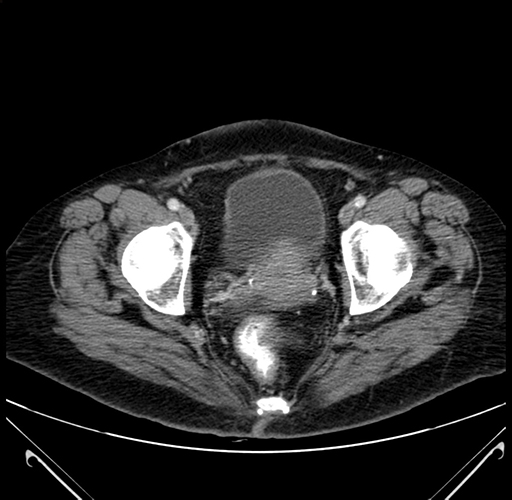

Pre-Chemo: Axial Venous

Axial Venous